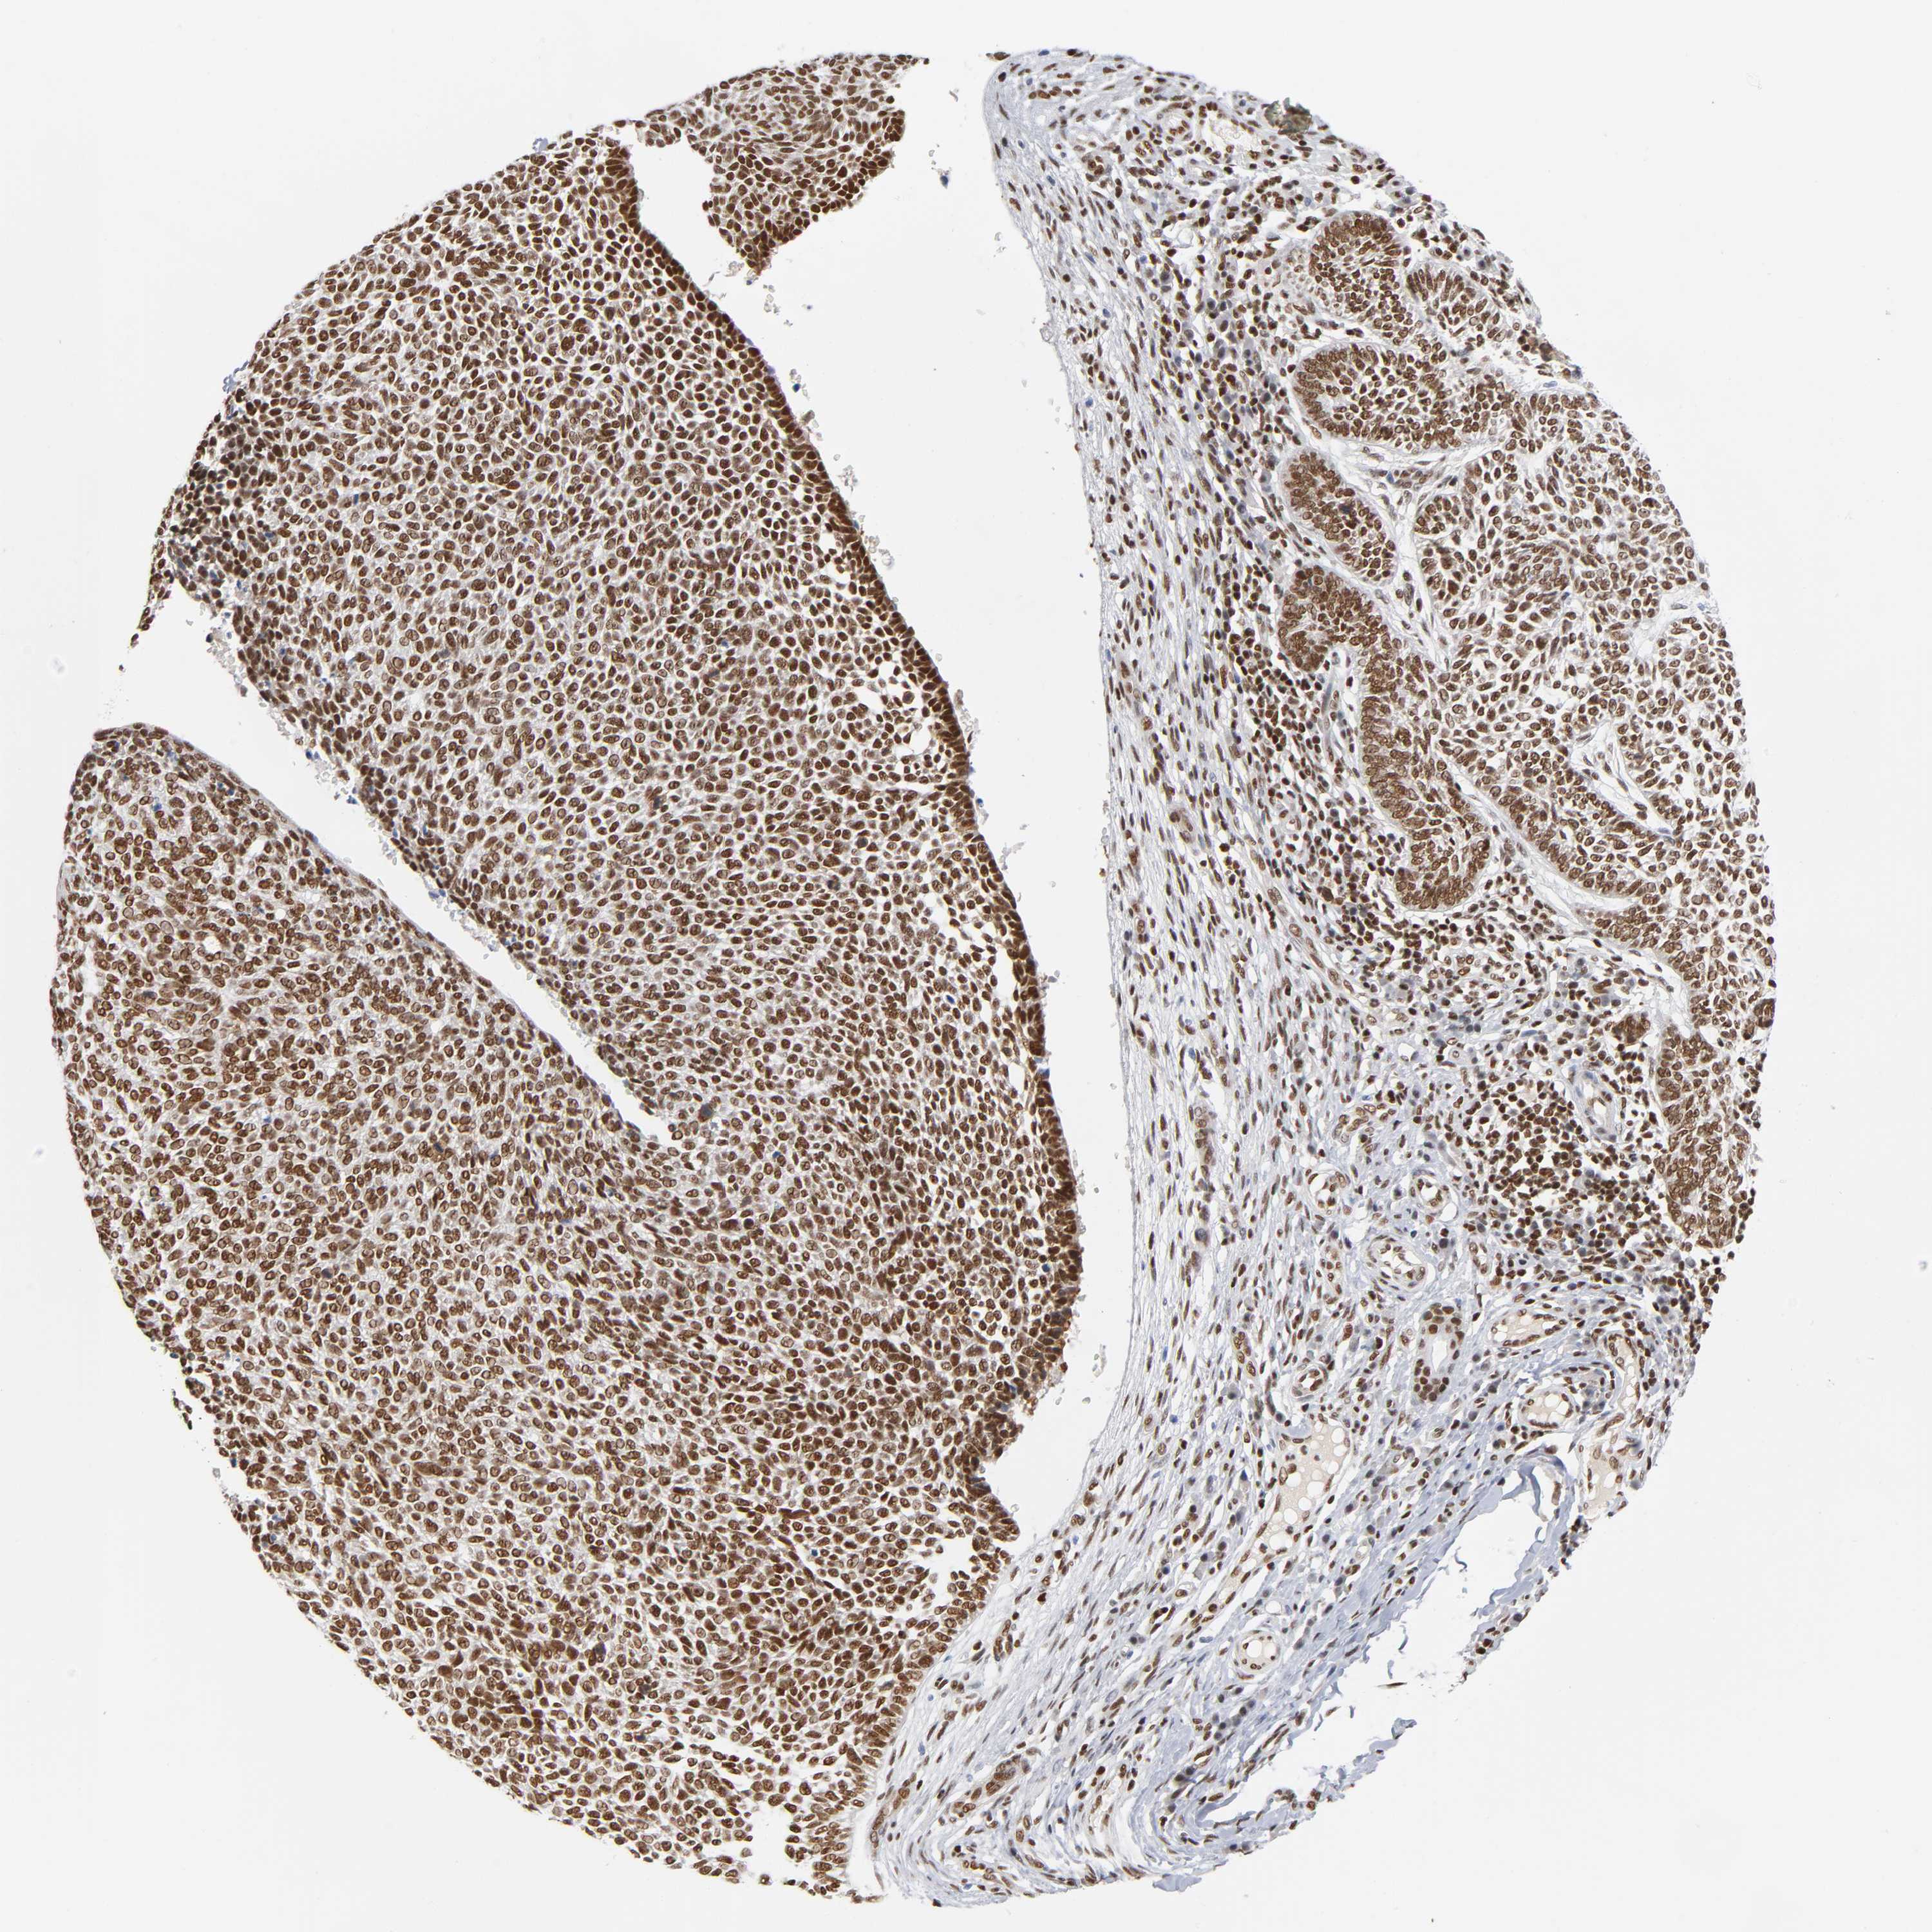

SKIN CANCER - Protein expressioni

A mouse-over function shows sample information and annotation data. Click on an image to view it in a full screen mode. Samples can be filtered based on level of antibody staining by selecting one or several of the following categories: high, medium, low and not detected. The assay and annotation is described here.

Antibody stainingi

Antibody staining in the annotated cell types in the current human tissue is reported as not detected, low, medium, or high, based on conventional immunohistochemistry profiling in selected tissues. This score is based on the combination of the staining intensity and fraction of stained cells.

Each image is clickable and will lead to virtual microscopy that enables deeper exploration of all samples and also displays staining intensity scores, fraction scores and subcellular localization as well as patient and tissue information for each sample.

Antibody HPA004752

Staining

High

Intensity

Strong

Quantity

>75%

Location

Nuclear

Squamous cell carcinoma, NOS

Basal cell carcinoma